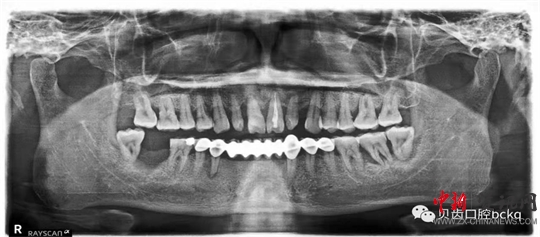

下面這兩張x光片是比較典型的牙周炎的影像資料。該患者的全口所有牙齒都出現(xiàn)了不同程度的松動(dòng)。患者現(xiàn)在感覺無法用牙齒咀嚼。坦白地講,牙周炎發(fā)展到這種程度,很多時(shí)候醫(yī)生也束手無策了。為了保留更多的牙槽骨,醫(yī)生回不得不拔掉哪些嚴(yán)重松動(dòng)的患牙。